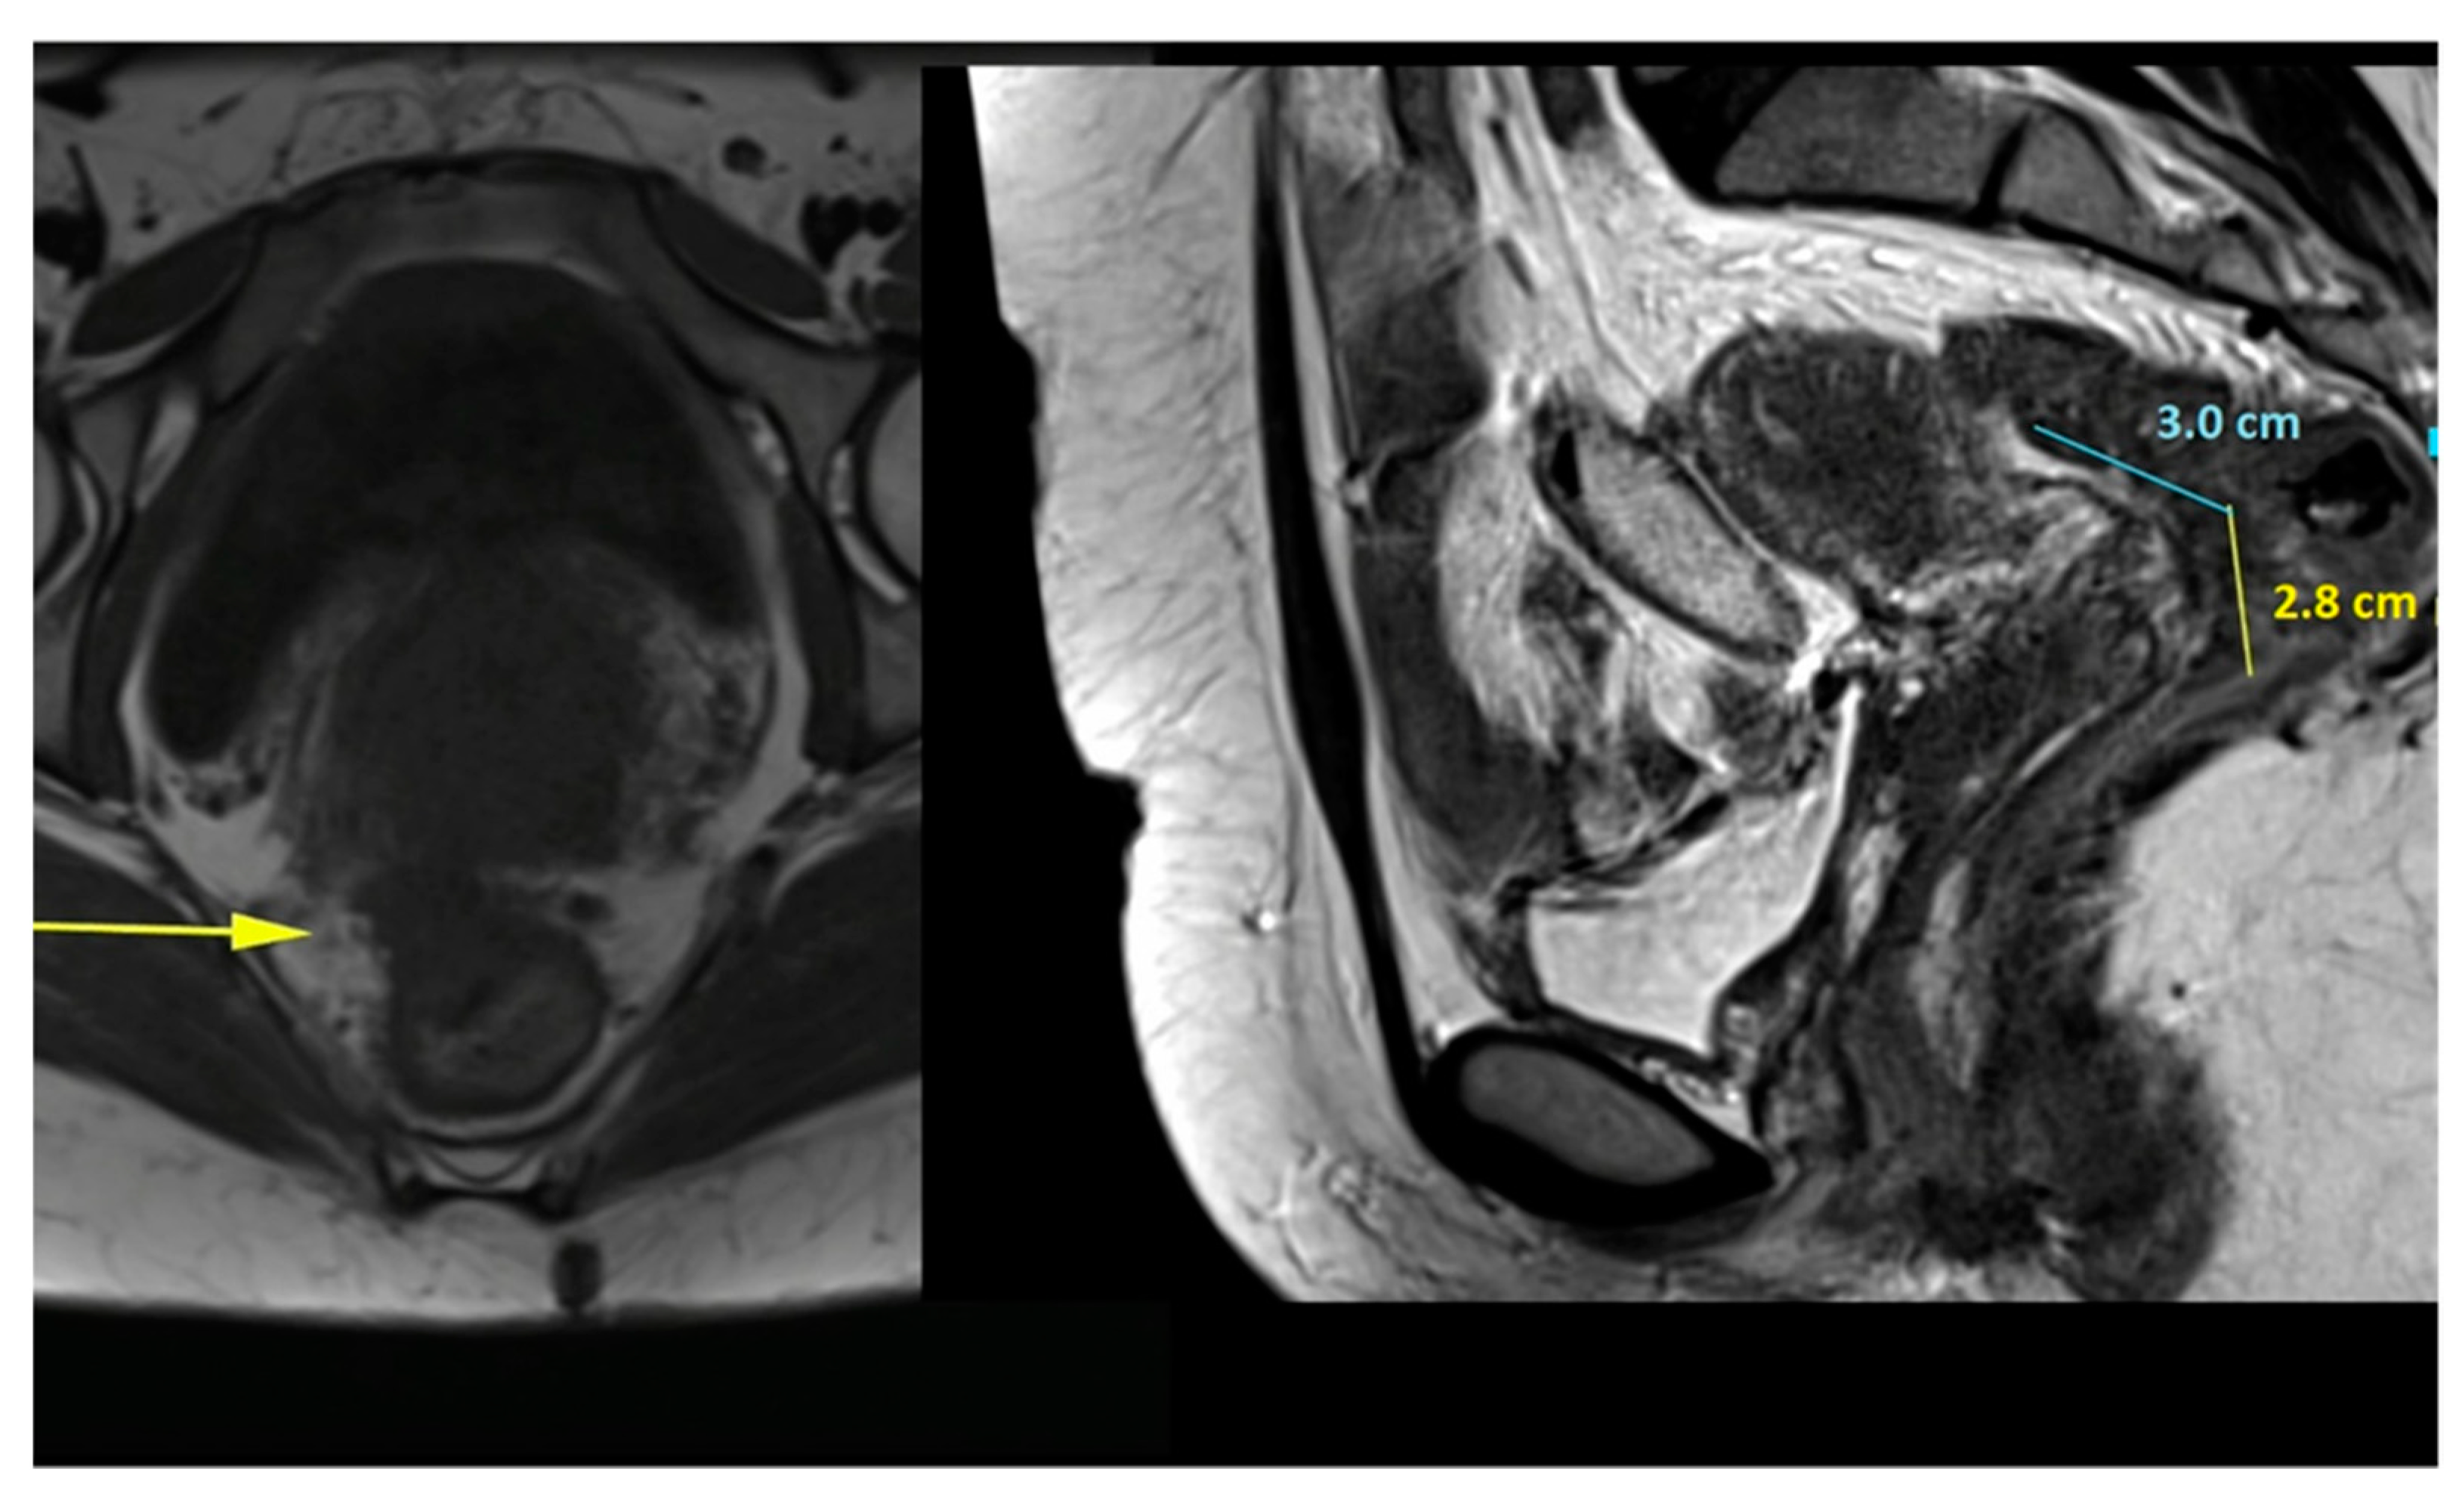

- The procedure starts with the inspection of the pelvic cavity and identification of the anterior rectal wall (Figure 2a,b).